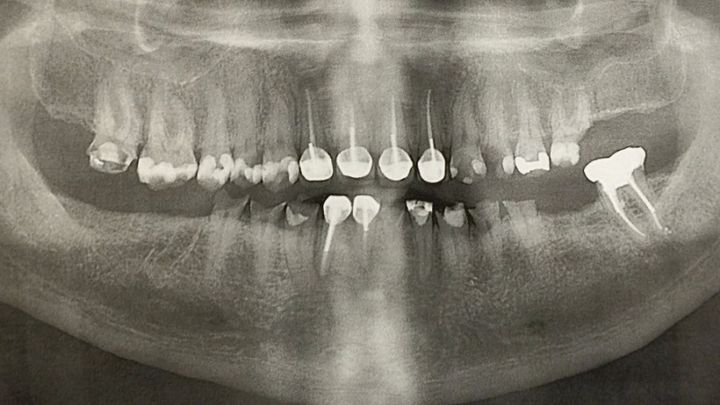

My name is Kristen Boland and I am starting this Go Fund me for my husband Shawn Boland because he not someone who would ever ask for help for himself. Shawn served in the United States Coast Guard from 2000-2005. He was stationed in Gloucester, Ma. on board a 110' patrol boat for 2 years, (He was there during the "Perfect Storm"). After Gloucester he went to the Coast Guard Station in Bodega Bay, Ca. driving the search & rescue boats for 3 years. During his time serving in the Coast Guard he suffered constantly from sea sickness. He told me that although he learned to be functional and do his job he never got over the nausea and vomiting. As a result the stomach acid quickly wore the enamel off of his teeth and started a process of erosion to the point that his teeth started to break and chip. He went to the Coast Guard dentist while he was still in and was told that there was nothing they could do about it. He recently spoke with the VA and was told that it is a very long process but also next to impossible to specifically get help with teeth. Over the years I have seen him suffer greatly with abscesses, root canals, broken teeth, extractions and difficulty eating. He has spoken with his dentist & oral surgeon and the only option is to remove all the remaining teeth. Then implants would be put in. Although we have double dental insurance we are told it will cost us about $60,000 out of pocket. Because of this, Shawn has put off starting this process for far too long because he feels guilty about putting his family, me and our two kids Shamus & Maisie, into that much debt. We have encouraged him to get the process started no matter the cost but he continues putting it off because of the financial burden.

It has now got to the point that it is causing more serious health issues. He has a swollen lymph node on the left side of his neck that won't heal because of the bacteria from his damaged teeth and recently the left side of his face swelled up and went partially numb and he had to have an emergency extraction to fix that. He has been having heart palpitations that his doctor cannot yet explain and we don't know if it is related to his teeth situation or not. Both his regular doctor & an ear-nose-throat specialist have said that this process needs to happen sooner rather than later. I am scared and I know he is too, so this go fund me is the only thing I could think of to help get this process started as quickly as possible and hopefully relieve his pain and some of the stress caused by trying to come up with $60,000 in a hurry. Shawn is an amazing husband and father, he works hard doing 12 hour shifts as a maritime dispatcher and drives 80 miles one way to get to work to support his family. I feel that after 5 years of going through seasickness and serving his country and saving lives he deserves to stop feeling anxiety and embarrassment about his teeth, to be able to eat normal food and to be healthy and not in pain all the time. I will be so glad to see him finally getting this problem taken care of and I know he will be so incredibly grateful for any help to make this happen. We are fully committed to doing this one way or another so that he'll be healthy and around for us for a long time to come. We are grateful for any help however small. Thank you everyone for taking the time to read this.

It has now got to the point that it is causing more serious health issues. He has a swollen lymph node on the left side of his neck that won't heal because of the bacteria from his damaged teeth and recently the left side of his face swelled up and went partially numb and he had to have an emergency extraction to fix that. He has been having heart palpitations that his doctor cannot yet explain and we don't know if it is related to his teeth situation or not. Both his regular doctor & an ear-nose-throat specialist have said that this process needs to happen sooner rather than later. I am scared and I know he is too, so this go fund me is the only thing I could think of to help get this process started as quickly as possible and hopefully relieve his pain and some of the stress caused by trying to come up with $60,000 in a hurry. Shawn is an amazing husband and father, he works hard doing 12 hour shifts as a maritime dispatcher and drives 80 miles one way to get to work to support his family. I feel that after 5 years of going through seasickness and serving his country and saving lives he deserves to stop feeling anxiety and embarrassment about his teeth, to be able to eat normal food and to be healthy and not in pain all the time. I will be so glad to see him finally getting this problem taken care of and I know he will be so incredibly grateful for any help to make this happen. We are fully committed to doing this one way or another so that he'll be healthy and around for us for a long time to come. We are grateful for any help however small. Thank you everyone for taking the time to read this.